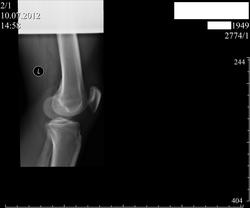

экзостоз на широком основании. нет периостита

Коллеги, огромное спасибо за помощь! Татьяна, какова должна быть тактика ведения пациента с экзостозом-консультация онколога или ортопеда?

Добавлены архивные снимки. Такое впечатление, что за год отсутствует существенная динамика.

Если клинически не беспокоит (по виду - не должно) - ничего не надо делать, наблюдайте дальше

Татьяна, что вы имеете ввиду, говоря наблюдайте дальше? Контрольные R- граммы? с какой частотой это делать- 1 раз в год?

да